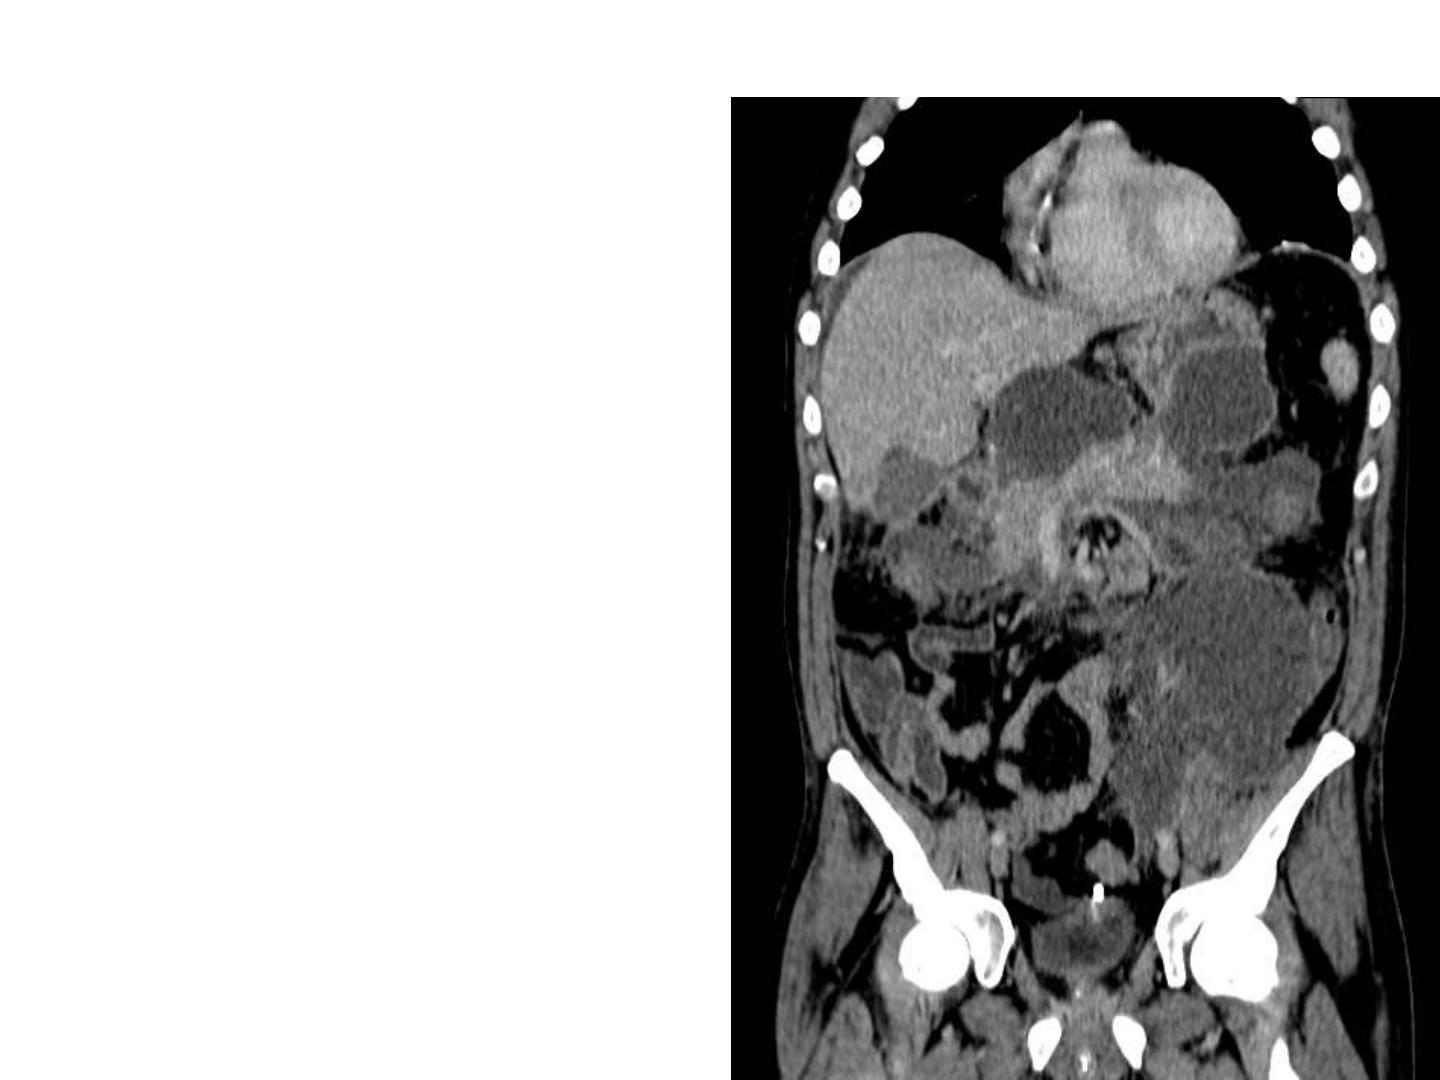

Exemple de cas

difficiles

Pancréatite aigüe

grave crosante

et surinfectée

Demande de

drainage

radiologique